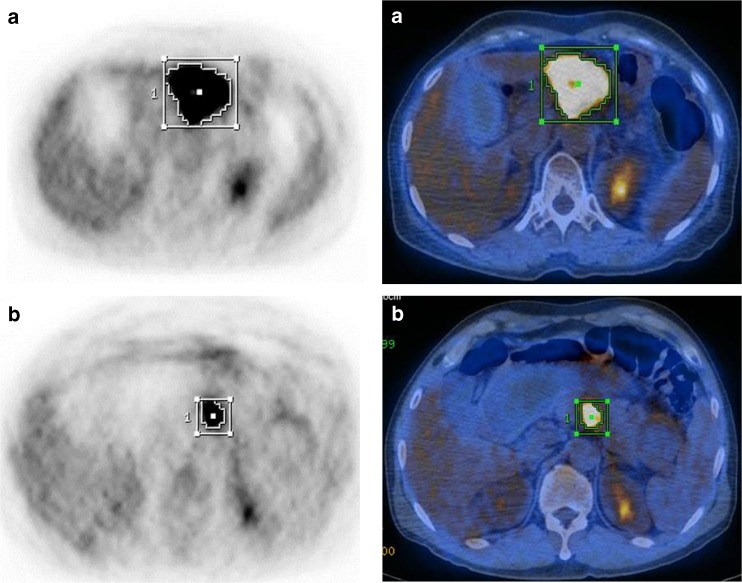

Fig. 2.

Representative 18F-FDG PET and PET/CT fusion images in high-MTV (a) and low-MTV (b) pancreatic neuroendocrine tumors (PNETs). a PET/CT of a 60-year-old male patient with a PNET that showed a high MTV (98.9 cm3) of the primary tumor, with a poor overall prognosis (overall survival = 13.6 months). b PET/CT of a 59-year-old male patient with a PNET that showed a low MTV (13.6 cm3) of the primary tumor, with a good overall prognosis (overall survival = 68.9 months)